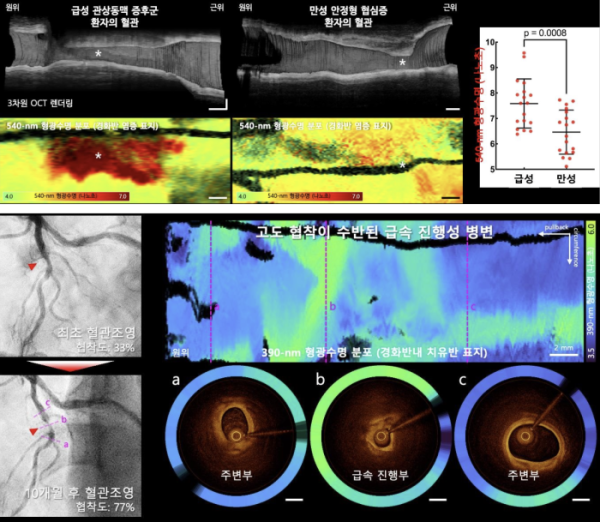

연구에서는 OCT-FLIm 융합영상기술을 활용해 기존 영상기법으로는 평가가 어려웠던 혈관 내 염증, 치유반, 칼슘 침착 등 동맥경화반의 병태생리학적 조성을 정밀하게 영상화하여 정량화했다. 병변 조성이 환자의 임상 상태와 밀접한 연관이 있다는 사실도 입증했다. 급성심근경색과 같은 급성 관상동맥 증후군 환자에서는 만성 안정형 협심증 환자보다 원인 병변의 혈관 염증 지표가 높게 나타났으며, 급속 진행성 병변에서는 반복된 경화반 파열과 치유의 흔적으로 인해 치유반이 광범위하게 분포하는 양상이 확인됐다. 이번 임상시험 과정에서는 모든 참여자에서 영상 획득이 안전하게 완료됐고, 별도의 합병증이나 부작용은 보고되지 않았다.